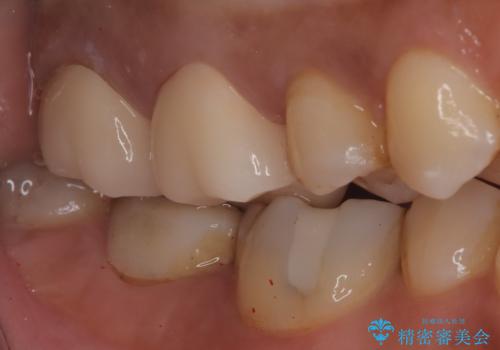

- 左上の奥歯がズキズキ痛い、冷たいものも長引く痛みがあると来院されました。

根管治療を行った後にオールセラミッククラウンにて修復しております。

根管治療を行った場合、破折リスクを軽減するために被せ物を行っております。